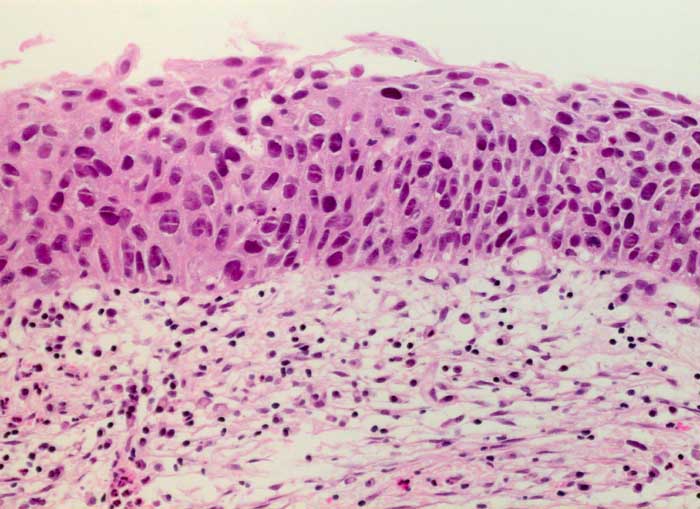

PathoPic ID 6212 - schwere Dysplasie des Plattenepithels CIN III

schwere Dysplasie des Plattenepithels CIN III

Portio

Portiobiopsie: Hyperchromatische und unregelmässig gelagerte Plattenepithelzellen mit vergrösserten Kernen. Lediglich minimale Ausreifung.

Leicht blutende Ektopie.

Histologie

200

36